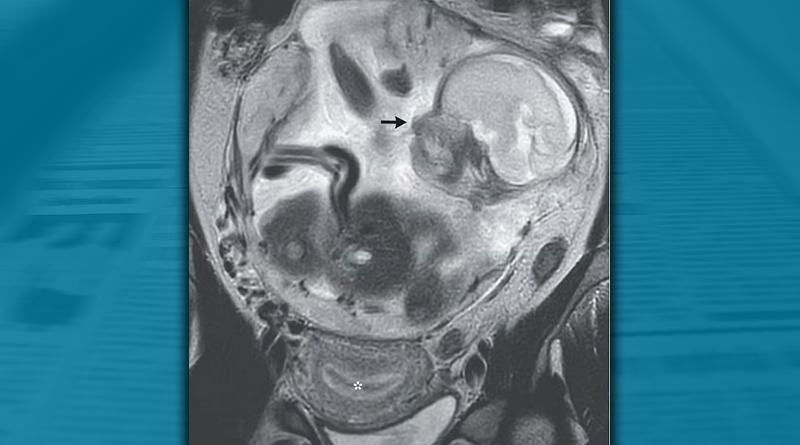

Apesar de ter um bebê de 23 semanas dentro do corpo, o útero da mulher estava completamente vazio. O feto havia se fixado na membrana que reveste a cavidade abdominal, logo acima do cóccix da mãe: um diagnóstico raro de gravidez abdominal. Devido ao alto risco de hemorragia materna e óbito fetal, a paciente foi transferida para um hospital de cuidados terciários.

Para a mulher, a visita oportuna ao pronto-socorro salvou sua vida. Uma ultrassonografia e uma ressonância magnética mostraram que, embora o revestimento do útero estivesse totalmente preparado para apoiar um embrião em crescimento, com o endométrio espesso, ninguém estava lá.